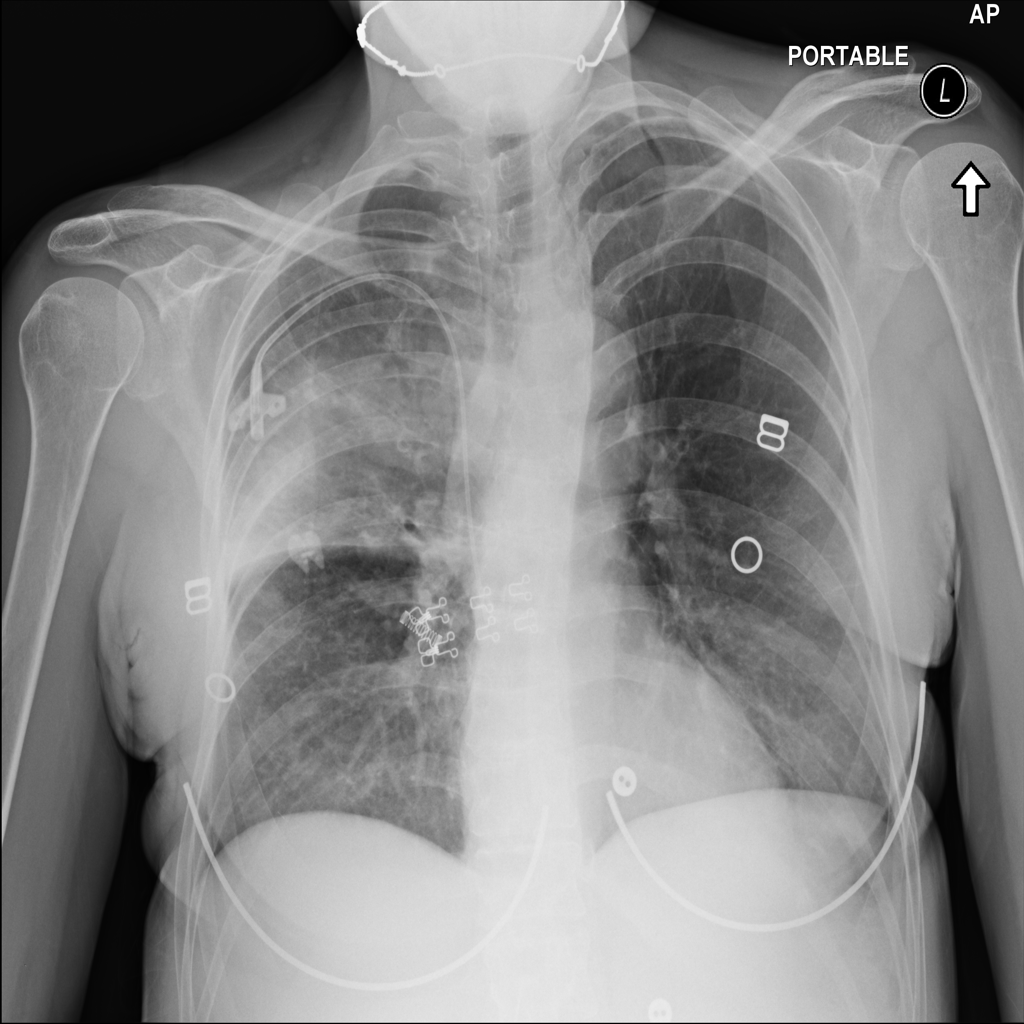

Consolidation

Consolidation refers to air-space filling that makes part of the lung appear denser on imaging.

Support Devices

Support devices on chest X-ray include lines, tubes, and implanted hardware whose position may affect safety and management.

Showing up to 90 reference images for Consolidation.

PAT-4DA0 · IMG-004Consolidation

PAT-4DA0 · IMG-004

AP